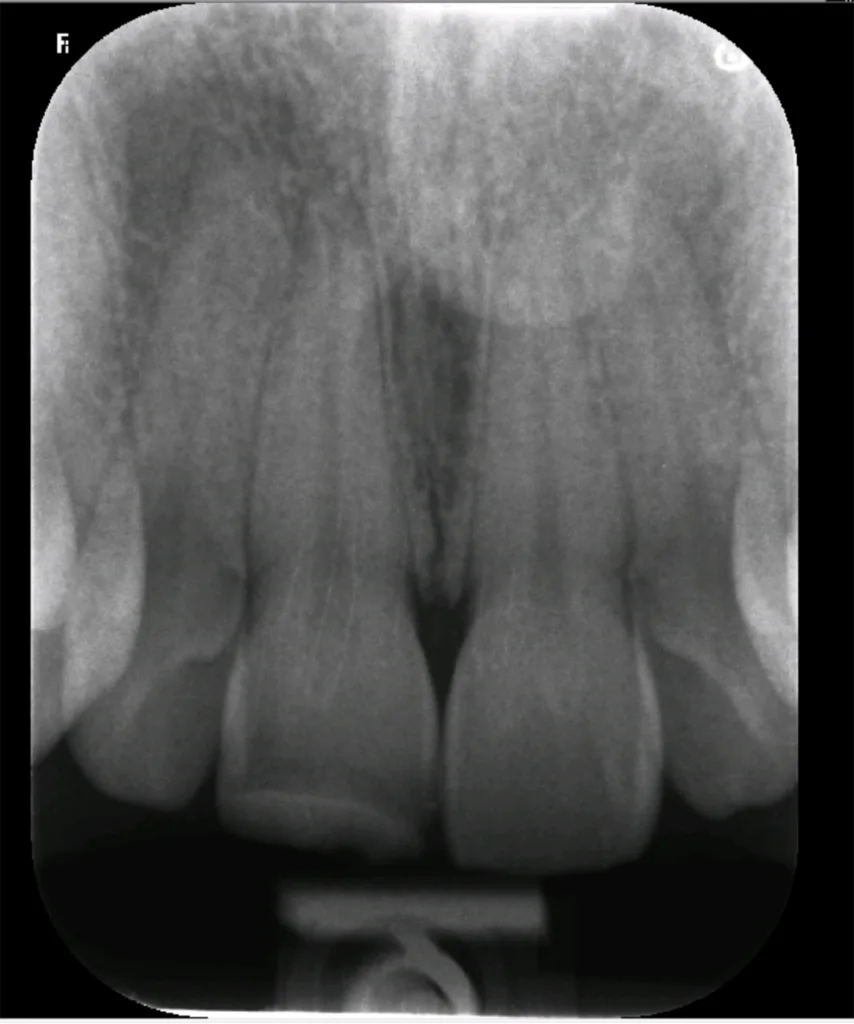

Ein 30-jähriger Patient mit unauffälliger Anamnese stellte sich mit dem Wunsch nach dem Austausch einer Kompositrestauration an Zahn 11 vor, die ihm zehn Jahre zuvor nach einem Trauma gelegt wurde. Bei der klinischen Kontrolle reagierte der Zahn positiv auf den Kältetest, und das Röntgenbild zeigte keine periapikalen Läsionen (Abb. 1). Allerdings fiel auf, dass der Schneidezahn verfärbt und im Vergleich zum Nachbarzahn 21 leicht nach palatinal geneigt war (Abb. 2).